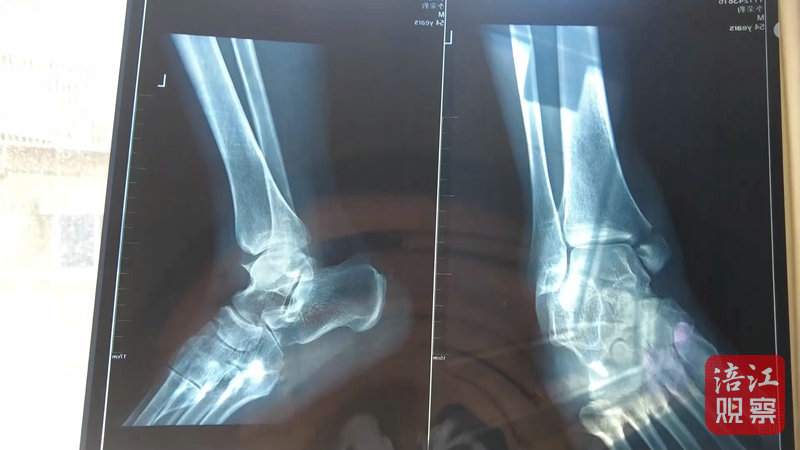

4月22日,記者來到綿陽市骨科醫(yī)院,病房內,李先生正在進行術后上下床的康復訓練。李先生的主治醫(yī)生介紹,李先生因左內踝骨折入院,手術一周后傷口愈合良好,病情穩(wěn)定,目前已轉入康復科進行康復功能鍛煉。